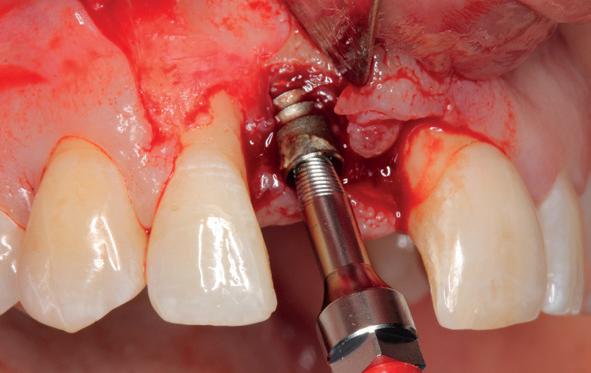

Implantologische behandelingen in het esthetische front vragen meer dan technische vaardigheid alleen. Ze vragen om overzicht, timing, vertrouwen en een team dat als vanzelf samenwerkt onder druk. Juist bij complexe casussen, waarin angst, infectie en hoge esthetische verwachtingen samenkomen, wordt zichtbaar hoe bepalend de rol van de tandartsassistent is.

Deze casus beschrijft een uitgebreide immediate implantaatbehandeling bij een patiënt die door meerdere collega’s werd geweigerd. Niet omdat de mogelijkheden ontbraken, maar omdat de complexiteit vroeg om een perfect afgestemde samenwerking. Het verhaal laat zien hoe de assistent in zo’n traject veel meer is dan een uitvoerende kracht of “mal”, maar een dynamische surgical guide die het proces mede stuurt, bewaakt en mogelijk maakt.De patiënt: wanneer alles samenkomt

Na het klinische onderzoek volgde het röntgenologisch traject. De CBCT liet precies zien wat we al vreesden: een front waarin het bot onregelmatig was, duidelijke radiolucenties rond de pijlers en een infectiegebied dat zich onder vrijwel de gehele brug had verspreid. Tegelijkertijd was er ook potentie. Net voldoende botstructuur om immediate implantaatplaatsing te overwegen, mits alles perfect gepland zou worden.